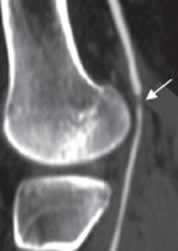

Fig 142 D. Erosión de la íntima.

AngioTAC reconstrucción sagital. Disminución del calibre de la arteria poplítea por erosión de la íntima, después de una luxación de rodilla reducida.